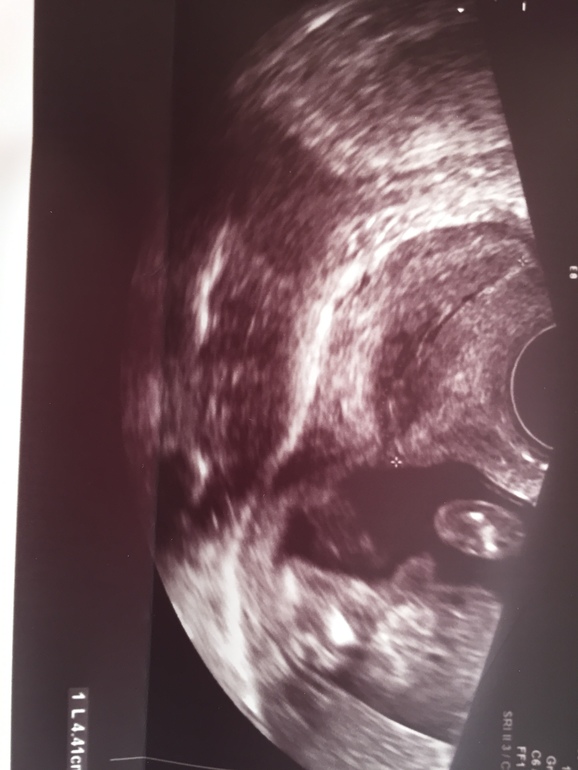

Но потом дома села снимки смотреть (ниже) и половой бугорок какой то слишком торчащим показался. Первое фото это снизу между ножек, сказали половые губки, а вот второе фото сбоку половой бугорок, он разве не мальчуковый? Срок 16.4

На таком сроке уже не плохо видно. Вероятность ошибки есть, но небольшая. Я бы верила узисту. На первом фото отлично видно половые губы. На втором - не половой бугорок, его уже нет, это что-то другое.

Второе фото это нога, ну или пуповина возможно, но никак не мальчукоый орган 😁. У вас девчуля, не переживайте